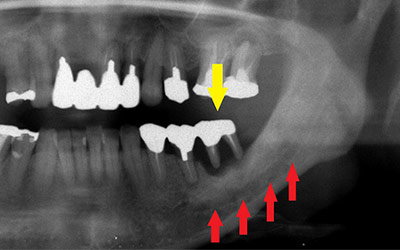

患者様の治療前のレントゲン写真です。写真の黄色矢印部の歯の周囲は、重度の歯周病で大きく歯槽骨が吸収されてしまっていました。そのため、写真の、赤色矢印で示す、下顎骨の中を通る神経までの距離がなく、インプラント埋入には、骨の高さが不足していました。

インプラントを埋入するためには、骨を増やさなければならず、患者様ご自身の骨を移植する、自家骨移植術を行なうこととしました。写真、青色の矢印で示す、智歯周辺の骨を採取し、黄色の矢印の部位に骨片を移植、チタン製の小さなスクリューで骨片を固定するという手術を行いました。細く、白く映っているのが骨を固定したミニスクリューです。